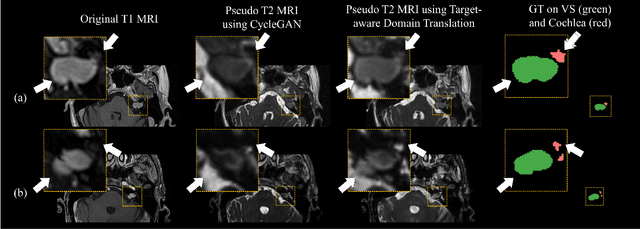

Abstract:Recent advances in deep learning-based medical image segmentation studies achieve nearly human-level performance when in fully supervised condition. However, acquiring pixel-level expert annotations is extremely expensive and laborious in medical imaging fields. Unsupervised domain adaptation can alleviate this problem, which makes it possible to use annotated data in one imaging modality to train a network that can successfully perform segmentation on target imaging modality with no labels. In this work, we propose a self-training based unsupervised domain adaptation framework for 3D medical image segmentation named COSMOS and validate it with automatic segmentation of Vestibular Schwannoma (VS) and cochlea on high-resolution T2 Magnetic Resonance Images (MRI). Our target-aware contrast conversion network translates source domain annotated T1 MRI to pseudo T2 MRI to enable segmentation training on target domain, while preserving important anatomical features of interest in the converted images. Iterative self-training is followed to incorporate unlabeled data to training and incrementally improve the quality of pseudo-labels, thereby leading to improved performance of segmentation. COSMOS won the 1\textsuperscript{st} place in the Cross-Modality Domain Adaptation (crossMoDA) challenge held in conjunction with the 24th International Conference on Medical Image Computing and Computer Assisted Intervention (MICCAI 2021). It achieves mean Dice score and Average Symmetric Surface Distance of 0.871(0.063) and 0.437(0.270) for VS, and 0.842(0.020) and 0.152(0.030) for cochlea.

Abstract:With the advances of deep learning, many medical image segmentation studies achieve human-level performance when in fully supervised condition. However, it is extremely expensive to acquire annotation on every data in medical fields, especially on magnetic resonance images (MRI) that comprise many different contrasts. Unsupervised methods can alleviate this problem; however, the performance drop is inevitable compared to fully supervised methods. In this work, we propose a self-training based unsupervised-learning framework that performs automatic segmentation of Vestibular Schwannoma (VS) and cochlea on high-resolution T2 scans. Our method consists of 4 main stages: 1) VS-preserving contrast conversion from contrast-enhanced T1 scan to high-resolution T2 scan, 2) training segmentation on generated T2 scans with annotations on T1 scans, and 3) Inferring pseudo-labels on non-annotated real T2 scans, and 4) boosting the generalizability of VS and cochlea segmentation by training with combined data (i.e., real T2 scans with pseudo-labels and generated T2 scans with true annotations). Our method showed mean Dice score and Average Symmetric Surface Distance (ASSD) of 0.8570 (0.0705) and 0.4970 (0.3391) for VS, 0.8446 (0.0211) and 0.1513 (0.0314) for Cochlea on CrossMoDA2021 challenge validation phase leaderboard, outperforming most other approaches.